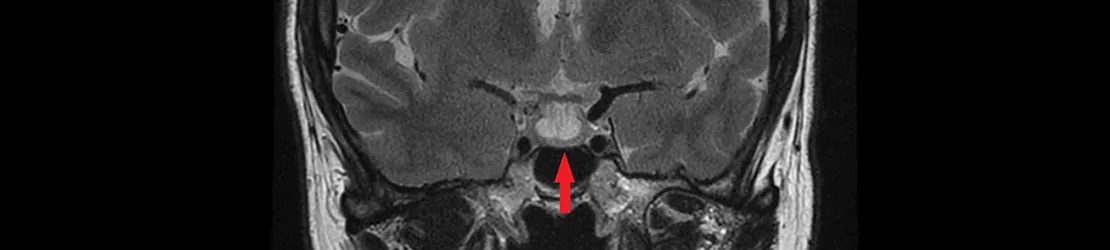

Scan RMN al creierului cu glanda hipofiza indicata printr-o sageata rosie

Diagnosticare

Dacă la un control medical sau la o investigație imagistică (CT, IRM) se suspectează diagnosticul de adenom hipofizar, pacientul va fi trimis la medicul specialist endocrinolog.

Pe lângă discuția cu pacientul și examinarea fizică, va fi necesară și recoltarea de sânge; în primă fază, vor fi evaluați toți hormonii hipofizari, precum și hormonii secretați de glandele controlate de hipofiză (prolactină, IGF1, ACTH, TSH, FSH, LH, Ft4, Ft3, testosteron, estradiol, cortizol). Ulterior, medicul va stabili dacă sunt necesare testări mai complexe (teste de stimulare sau supresie), pentru a confirma diagnosticul.

Cea mai utilă investigație imagistică (care vizualizează adenomul) este rezonanța magnetică nucleară (IRM) de hipofiză cu substanță de contrast. Aceasta va permite stabilirea dimensiunilor adenomului, efectelor acestuia asupra structurilor din jur și urmărirea periodică (la 6 – 12 – 24 de luni) a evoluției adenomului.